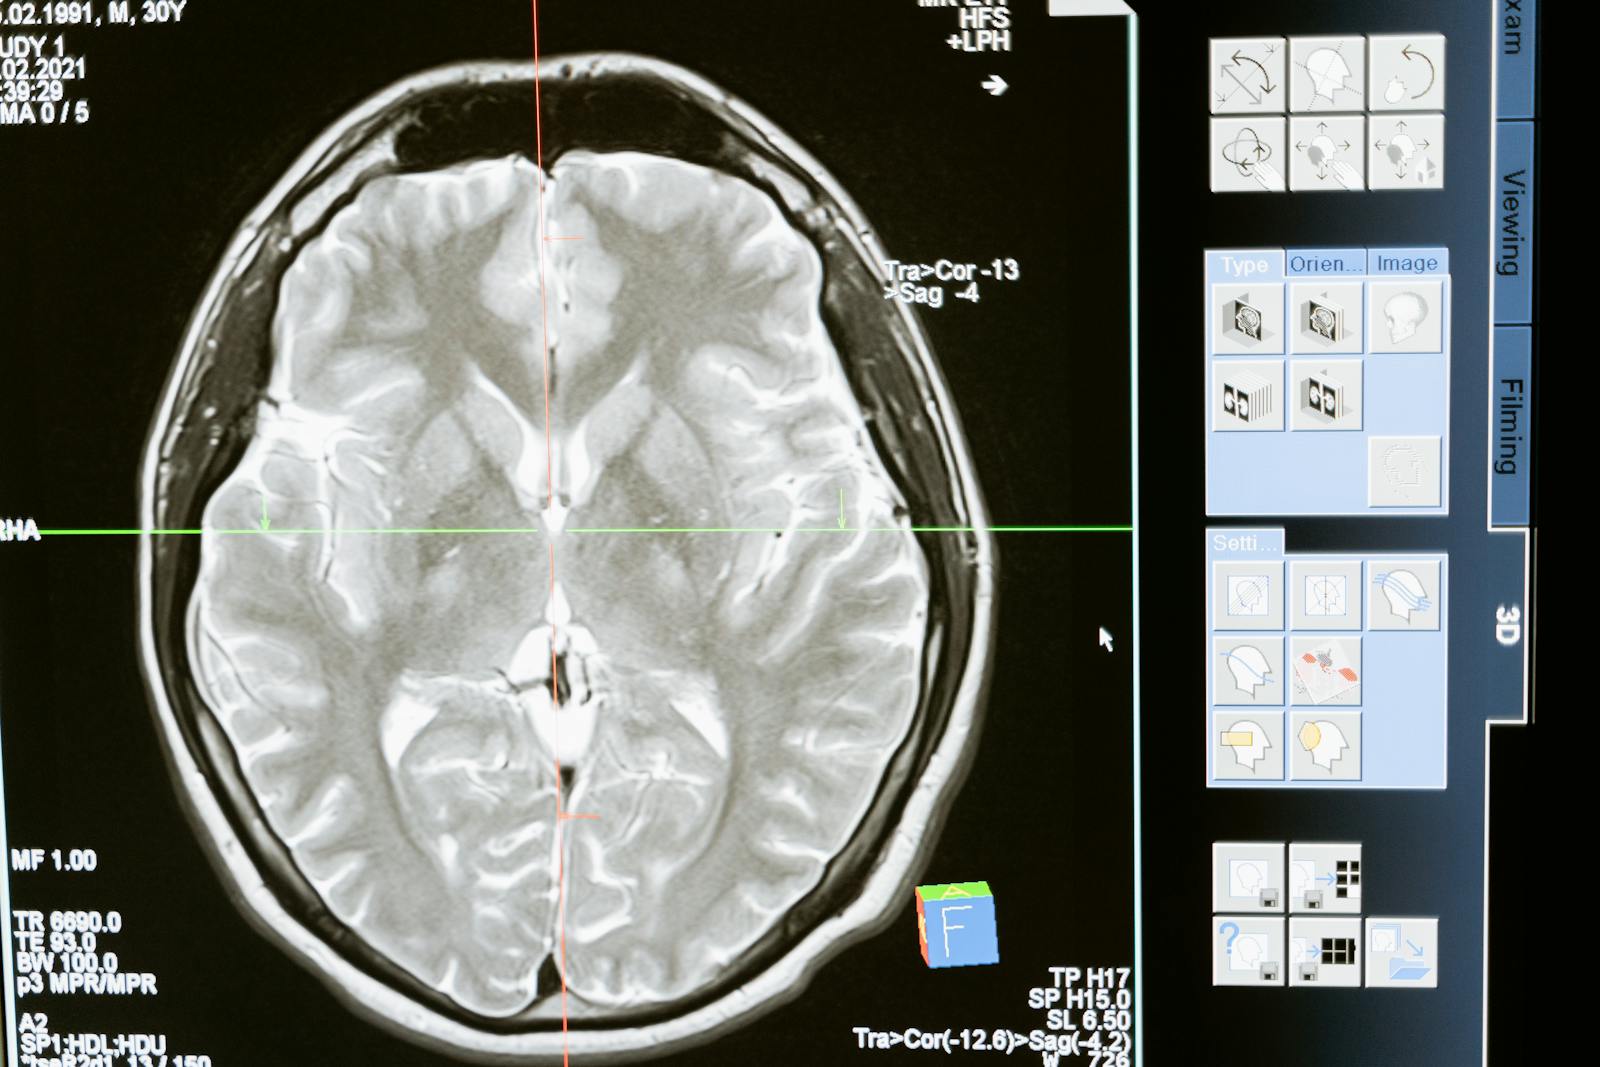

Laboruntersuchungen und Bildgebung:

In den meisten Fällen sind für die Diagnose einer leichten geistigen Behinderung keine spezifischen Laboruntersuchungen oder bildgebenden Verfahren erforderlich. Die Diagnose stützt sich in erster Linie auf die klinische Beurteilung und standardisierte kognitive Tests. Es gibt jedoch Situationen, in denen zusätzliche Tests durchgeführt werden können, um zugrunde liegende Ursachen oder beitragende Faktoren zu identifizieren:

● Bildgebende Untersuchungen: Bei Verdacht auf strukturelle Anomalien des Gehirns, die zu einer geistigen Behinderung beitragen, können bildgebende Verfahren wie MRT (Magnetresonanztomographie) oder CT (Computertomographie) durchgeführt werden.